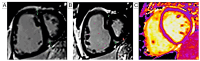

Pulmonary hypertension (PH) is a life-threatening cardiopulmonary disease associated with a poor prognosis, with progressive right ventricular (RV) failure being the main cause of death in this vulnerable population. Right heart catheterization remains the gold standard for assessing pulmonary hemodynamics. However, due to its invasive nature, non-invasive imaging methods are gaining increasing interest. Two-dimensional transthoracic echocardiography serves as the primary screening tool for PH and is widely used to estimate its likelihood. Nevertheless, this technique has several limitations, partially addressed through the assistance of a three-dimensional echocardiography. Cardiac magnetic resonance imaging (CMR) provides a comprehensive evaluation of both the morphology and hemodynamics of right ventricle-pulmonary artery unit, offering essential information for diagnosis, prognosis, and therapeutic monitoring. While two-dimensional cardiac CMR enables non-invasive characterization of pulmonary hemodynamics, advances in 4D-flow cardiac CMR allow for a more detailed analysis. These advancements enable the assessment of flow patterns, energetics, wall shear stress and severity, offering a more nuanced understanding of the disease. This review aims to provide an in-depth summary of the current data on advanced non-invasive imaging techniques for PH.